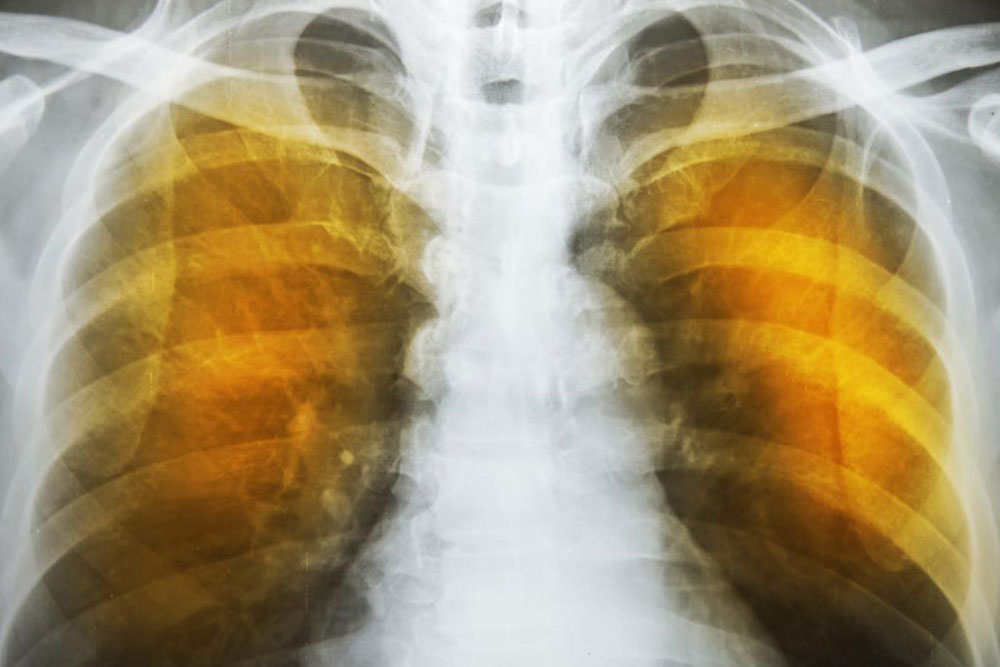

Emphysema – Symptoms, Causes, and Management Options

Emphysema is a disease that causes the destruction of the air sacs in the lungs. It can lead to shortness of breath, chronic coughing, and wheezing. The best way to prevent emphysema is to limit or completely avoid exposure to dust, fumes, or other harmful chemicals. That said, when one is at risk of developing emphysema due to family history or work, it is important to consult a doctor to understand how to manage it.

Emphysema is caused by a loss of elasticity in the lungs. This can happen when the lung tissue is damaged or destroyed, which can be due to inhalation of harmful gases and pollutants. The condition also develops when the walls of the alveoli in the lungs become damaged and start to get inflamed, restricting the oxygen flow to the bloodstream. As the disease progresses, it may become difficult for one to breathe or walk more than a short distance without resting.